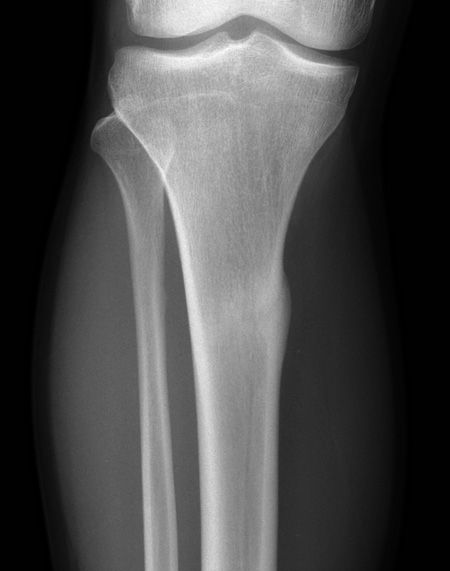

Transverse cortical stress fracture of the tibia

TRAUMA X-RAY 71: Gymnast with pain in lower leg. What is the abnormality? Answer https://t.co/MvjB5A3H4C